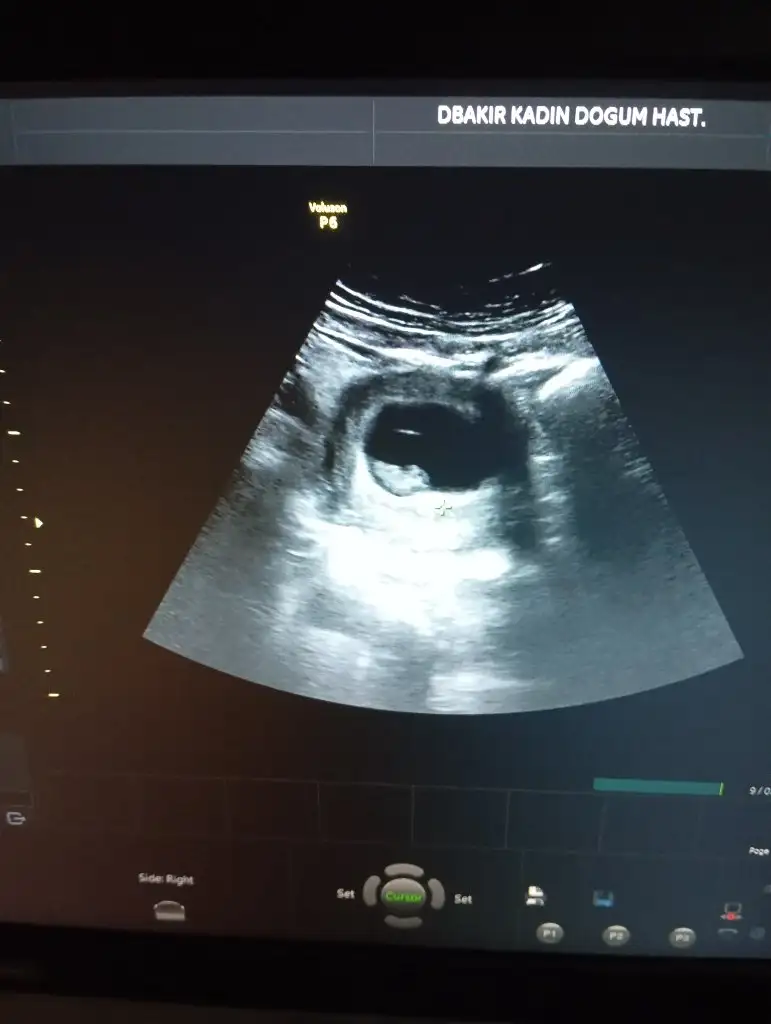

Karından çekildi 6 haftalık yorumlarmisin lütfenErkek canım

Karından bakıldıysa eğer,

Soldan girmiş gözüküyosa gerçektede solmuş ve ERKEK,

Sağdan girmiş gözüküyosa gerçekte de sağmış ve KIZ,